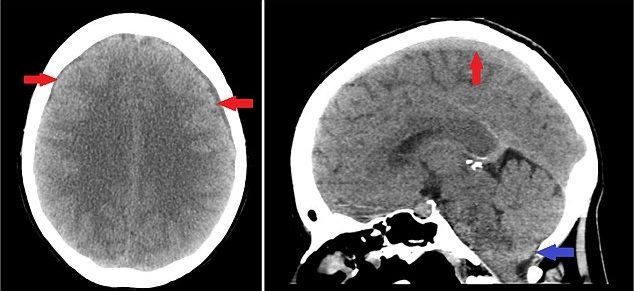

Ecco come appariva l’esame della signora che lamentava i forti mal di testa, dovuti alla fuoriuscita di liquido nel cervello.